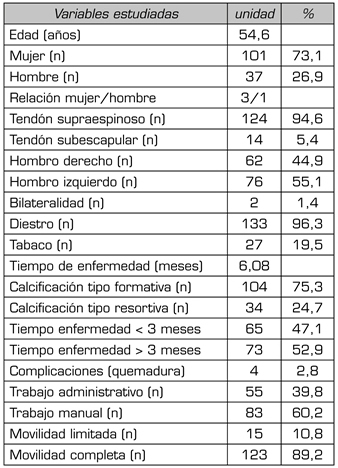

Results: Mean age 54.6 years (n = 138). Female (73.1 %; n = 101); female to male ratio 3:1. Supraspinatus tendon (94.6 %; n = 124), subscapularis (5.4 %; n=14); left shoulder (55.1 %; n = 76), right shoulder (44.9 %; n = 62). Bilateral 1.4 % (n = 2). Right handed 96.3 % (n = 133); Personal history: smoking (19.5 %; n = 27), diabetes (7.2 %; n = 10); disease time averaged 6.08 months; acute-subacute pain (less than 3 months) 47.1; (n = 65), chronic pain (greater than 3 months) 52.9 % (n = 73). Radiological type: formative 75.3 % (n = 104); resorptive 24.7 % (n = 34). Average number of sessions: 20.5. Treatment complications 2.8 % (n = 4): intolerance/erythema/burn. Occupation: administrative 39.8 % (n = 55), manual jobs 60.2 % (n = 83).

Average initial pain 7.3 points (VAS scale), significantly decreased (p = 0.0000) post treatment to 2.7. Initial average size of calcifications 10.7 mm and significantly decreased (p = 0.0000) post treatment to 3.8 mm. Change of calcification: success/cure rate 55.7 % (n = 77), improvement rate 20.2 % (n = 28); failure rate 23.9 % (n = 33). Functional limitation decreased from 10.8 % of patients to 2.1 %.

Resultados: Edad media: 54,6 años (n = 138); mujer (73,1 %; n = 101); proporción mujer/hombre 3: 1; tendón supraespinoso (94,6 %; n = 124); subescapular (5,4 %; n = 14); hombro izquierdo (55,1 %; n = 76), hombro derecho (44,9 %; n = 62); bilateral 1,4 % (n = 2); diestros 96,3 % (n = 133); antecedentes personales: tabaquismo (19,5 %; n = 27), diabetes (7,2 %; n = 10). El tiempo de enfermedad promedio fue de 6,08 meses. Dolor agudo-subagudo (menos de 3 meses) 47,1 %; (n = 65), dolor crónico (más de 3 meses) 52,9 % (n = 73). Tipo radiológico: formativo 75,3 % (n = 104), resortivo 24,7 % (n = 34). Número promedio de sesiones: 20. Complicaciones del tratamiento 2,8 % (n = 4): intolerancia/eritema/quemadura. Ocupación: administrativo 39,8 % (n = 55), trabajos manuales 60,2 % (n = 83). El dolor inicial EVA de 7,3 puntos disminuyó significativamente (p = 0,0000) después del tratamiento a 2,7. El tamaño promedio inicial de las calcificaciones fue de 10,7 mm y disminuyó significativamente (p = 0,0000) después del tratamiento a 3,8 mm. Cambio de calcificación: tasa de éxito/curación 55,7 % (n = 77), tasa de mejora 20,2 % (n = 28); tasa de fracaso del 23,9 % (n = 33). La limitación funcional disminuyó de un 10,8 % a un 2,1 %.

La edad de los pacientes de la muestra ha sido 54,6 años (n =1 38). El sexo más frecuente ha sido el femenino (73,1 %; n = 101), con una relación mujer/hombre de 3/1 (Tabla I). Entre los antecedentes asociados a la TC, destacaba el tabaquismo (19,5 %; n = 27) y la diabetes (7,2 %; n = 10) (Tabla I).

Tabla I. Evaluación de las principales variables estudiadas (n = 138)

El tendón más afectado ha sido el del supraespinoso (94,6 %; n = 124), seguido del tendón del subescapular (5,4 %; n = 14) (Tabla I). En cuanto a la lateralidad, el hombro más frecuentemente afectado ha sido el izquierdo (55,1 %; n = 76), seguido del derecho (44,9 %; n = 62). Solo dos pacientes presentaron TC bilateral (1,4 %; n = 2) (Tabla I). Con respecto a la dominancia, la mayoría de los pacientes eran diestros (96,3 %; n = 133).

El tiempo de enfermedad en este estudio fue en promedio de 6,08 meses. El dolor agudo-subagudo (menor de 3 meses) era menos frecuente (47,1 %; n = 65) que el dolor crónico (mayor de 3 meses) (52,9 %; n = 73) (Tabla I).

El tipo radiológico más frecuente fue el formativo (75,3 %; n = 104), seguido del resortivo (24,7 %; n = 34). El número promedio de sesiones aplicadas fue de 20,5. Un 2,8 % de los pacientes (n = 4) abandonaron el tratamiento debido a intolerancia, eritema y/o quemadura, por lo que completaron el tratamiento con ultrasonido u onda corta según tolerancia (para el manejo del dolor). Con respecto a la ocupación, un 39,8 % (n = 55) eran administrativos, mientras que el 60,2 % (n = 83) realizaban trabajos manuales (Tabla I).

Con respecto a la movilidad, el 10,8 % (n = 15) de los pacientes presentaron limitación funcional en el hombro afectado (Tabla I).